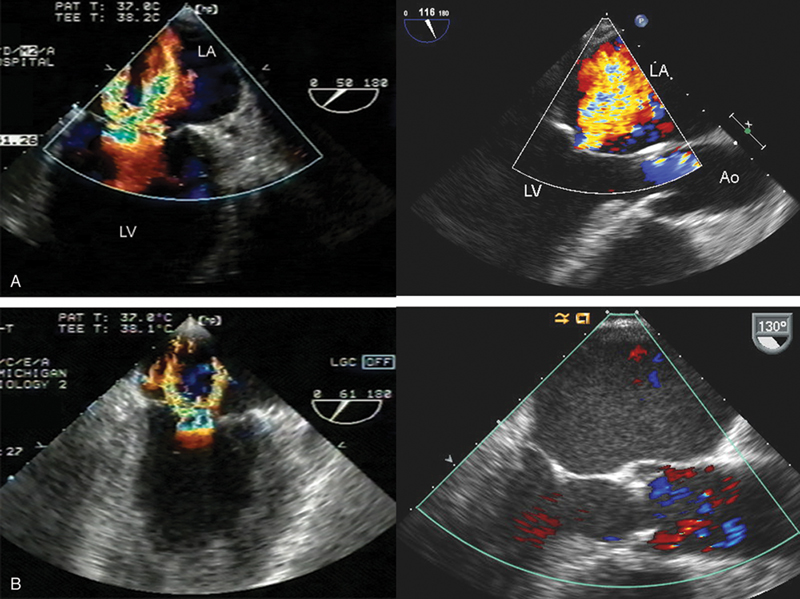

فحوصات تشخيصية لبعض امراض القلب والشرايين التاجية